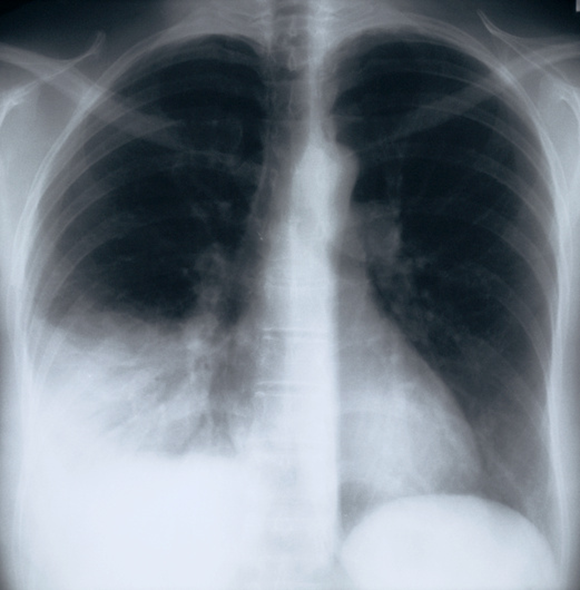

בצילום רנטגן של הילד החולה, דלקת הריאות שהוא סובל ממנה נראית בלבן – זה לא סימן ל"מחלת ריאות לבנות" מסתורית. צילום חזה של מטופל עם דלקת ריאות, שנראית בלבן בחלק השמאלי התחתון של הצילום | CNRI / Science Photo Library

מתברר שאין דבר כזה מחלת "הריאות הלבנות". כפי שהוסבר בדיווח ברשת NBC, מדובר בכותרת שתפסה אחיזה ולא במינוח רפואי. בצילום רנטגן של הילד החולה, דלקת הריאות שהוא סובל ממנה נראית בלבן. זה הכול – עיתונאי ניסח כותרת ואנשים משתמשים בה בתור מושג. הילדים חולים בסוגים שונים של דלקות ריאה, ואין כל קשר בין המחלות שלהם לבין המתרחש בסין, כך טוענים המומחים באוהיו. העליה במספרי החולים בתקופה זו של השנה דומה לעליה שהייתה בכל שנה עד פרוץ מגפת הקורונה, ואין בה באמת משהו חריג, מלבד הרגישות של התקשורת והציבור להתפשטות של תחלואה. דלקות הריאה בשתי המדינות בארצות הברית נגרמות מגורמים ידועים, חיידקיים או נגיפיים דוגמת נגיף ה-RSV. בחלקם ניתן לטפל באנטיביוטיקה ואין צורך באשפוז. מה ניתן לעשות כדי למנוע התפשטות? כרגיל בתחלואת חורף: לדאוג להיגיינה, לכך שחולים יישארו בבית ולא ילכו לבית הספר או לעבודה, ולהתחסן נגד מה שאפשר, מפני שחלק ממקרים אלה הם סיבוכים מאוחרים יותר של מחלה נגיפית כמו שפעת.